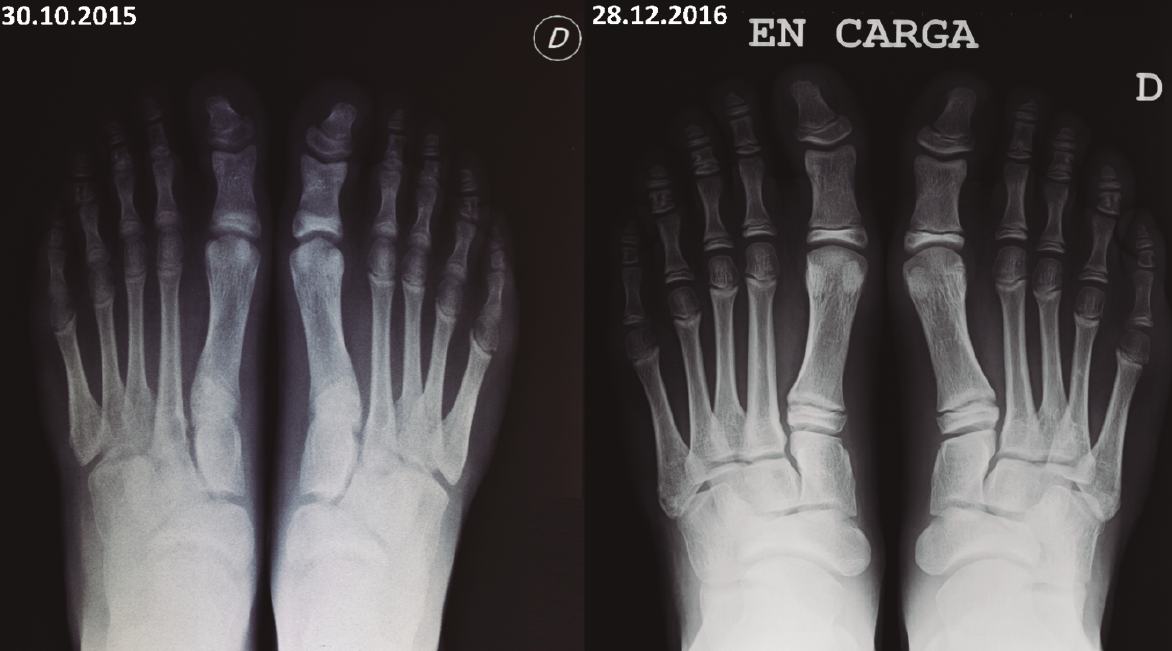

Figura 3. Radiografías dorsoplantares en carga. Control de la evolución del navicular desde la primera consulta hasta un año después de instaurar el tratamiento conservador.

Solicitamos radiografías de ambos pies en carga con proyecciones dorsoplantar (Figura 3) y de perfil (Figura 4). En la primera observamos una displasia en forma de coma en el hueso navicular de ambos pies, así como su evolución tras un año de haber instaurado el tratamiento conservador.

Un año después de instaurar el tratamiento, el paciente no refiere molestias y ha reanudado su práctica deportiva con normalidad, para lo cual fabricamos plantillas indicadas para la práctica del fútbol. Los objetivos son los ya explicados, aunque, en este caso y teniendo en cuenta el ajustado calzado propio del fútbol, así como el gesto deportivo, optamos por utilizar de base un polipropileno de 2 mm, añadiendo cuñas pronadoras totales. En las radiografías de control, se aprecia una evidente mejoría morfológica del navicular, presentando un mayor grosor en su tercio lateral, sin forma “de coma”: la anatomía radiológica es prácticamente normal.